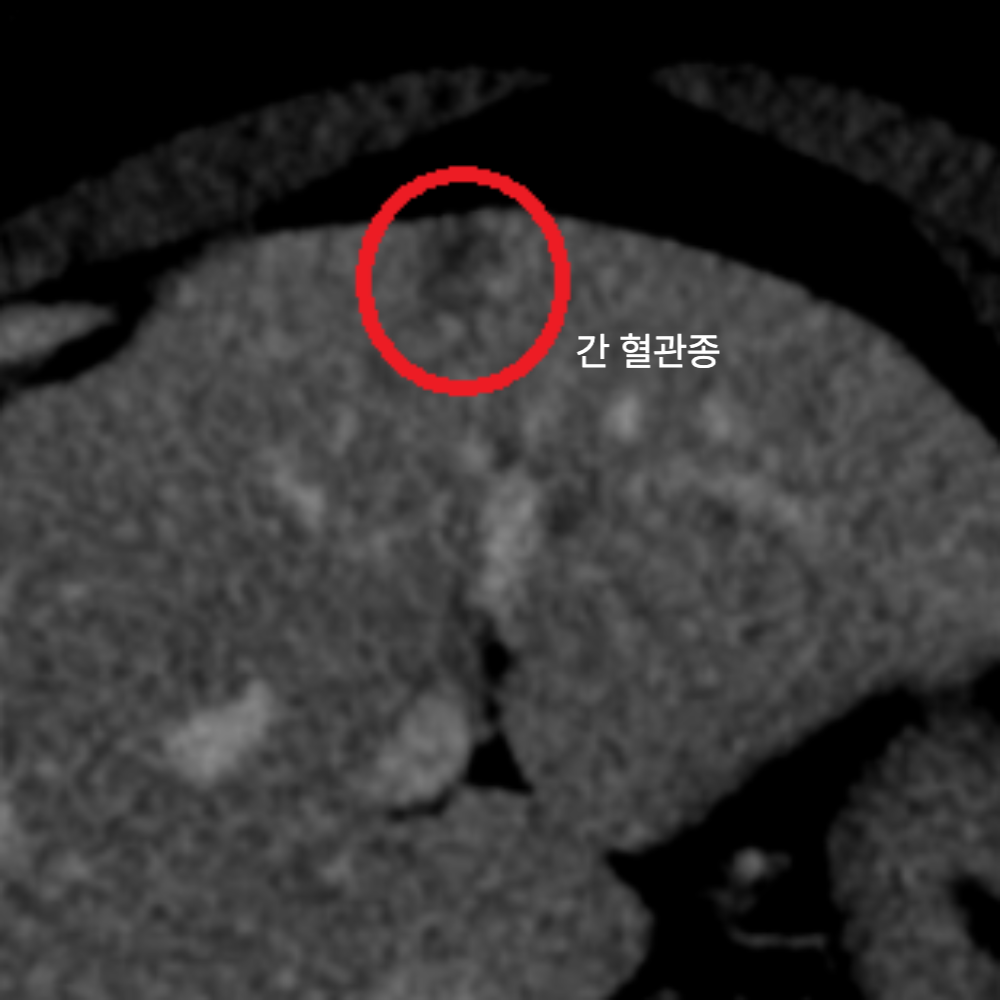

2. 간염 & 간농양 &간암